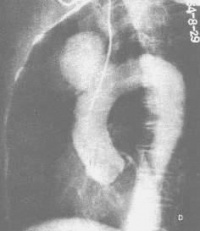

1.X线表现:

(l)纵隔阴影增宽或形成局限性块影,至少在某一个体位上,与胸主动脉某部相连而不能分开。一般升主动脉瘤位于纵隔的右前方,弓降部和降主动脉动脉瘤多位于左后方。

(2)肿块或纵隔增宽阴影可见扩张性搏动。

(3)瘤壁有时可有钙化

(4)瘤体(尤其囊状)可压迫侵蚀周围器官,例如压迫脊椎或胸骨的侵蚀性骨缺损,有助于动脉瘤的诊断。

胸部X线片(后前位及左侧位)十分有用,可显示大多数胸主动脉瘤,透视有助于与其他纵隔肿物相鉴别。但有些胸主动脉瘤甚小,尤其是囊状动脉瘤破裂后在X线片中难以发现。所有准备施行手术的术前均应进行主动脉造影,因其可清晰地显示动脉瘤的大小范围。数字减影血管造影(DSA)有可能替代主动脉造影,但它对小动脉的显彰较差,且易受运动的影响。CT增强扫描可显示升主动脉及降主动脉瘤,有助于诊断。二维超声检查对胸主动脉瘤(尤其是降主动脉瘤)的诊断准确性不如腹主动脉瘤。经食管UCG—TEE则对胸主动脉瘤的诊断有较大的价值。MRI对胸主动脉瘤可作出可靠的诊断。